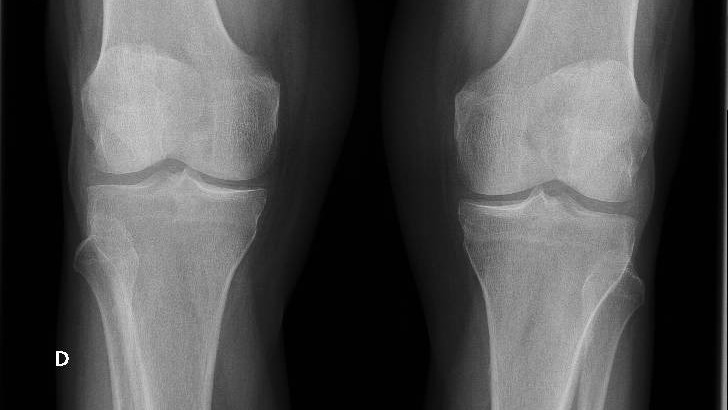

Radiografía de rodillas y manos: signos de condrocalcinosis.

Dada la falta de respuesta a la antibioterapia, se realizó una ecografía descartándose TVP. Ante la posibilidad de que el cuadro se tratara de un brote de artritis, se solicitaron cifras de ácido úrico que fueron normales, se realizó estudio de radiografía simple de rodillas y muñecas donde se evidenciaron datos de condrocalcinosis, haciendo probable el diagnóstico de enfermedad por depósito de pirofosfatos.